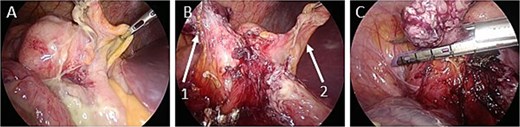

The operation was performed laparoscopically. The ileocecal area was compressed in the cephalad region due to an enlarged uterus. Contaminated ascites was observed around the ileocecal area (Fig. 2A). An enlarged appendix was identified dorsal to the ileocecal area. The appendix was resected using an automatic suture device (Fig. 2B and C).

Intraoperative images. (A) There is contaminated ascites around the ileocecal area. (B) The appendiceal mesentery and appendiceal artery are dissected (arrow 1: appendix; arrow 2: ileocecal fold). (C) The appendix is dissected with an automatic suture device.